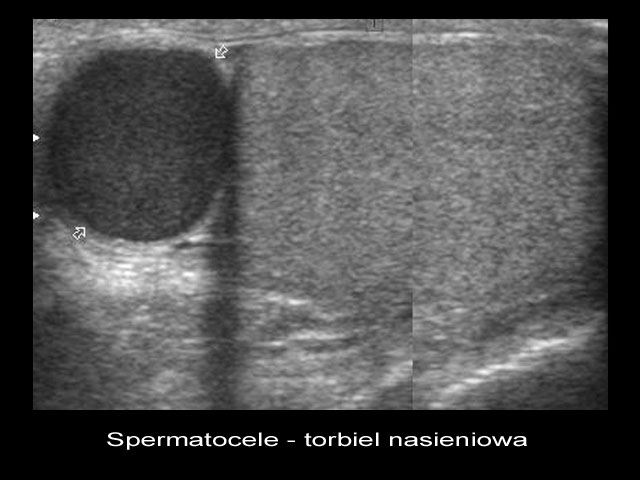

- Obecności zmian patologicznych - np. torbiele, guzki, zwapnienia.

- Zapalenie jądra lub najądrza